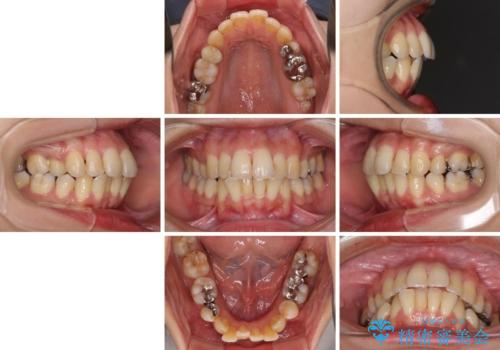

- 抜歯矯正の後戻りで前歯が突出してきていることを気にして来院された患者様です。

口元の突出感を改善するにあたり、抜歯矯正は行うことができないため、奥歯の後方移動とIPR(歯と歯の間を削る)により達成することとしました。

再度後戻りしたときに対応しやすいよう、インビザラインにて矯正治療を行うこととしました。

舌の突出癖がなかなか改善できず、IPRによる前歯の隙間が閉じきらずに、予定よりも長い治療期間となりました。